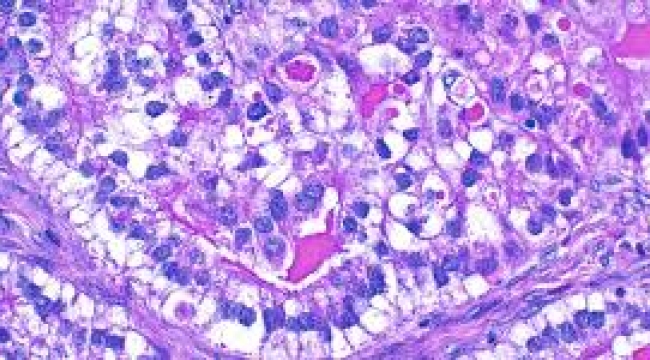

Çinli bir bilimsel araştırma ekibi, kanserin patolojik görüntülerini detaylı okuyabilen çok yönlü bir yapay zeka modeli geliştirdi. Çin'de bulunan Hava Kuvvetleri Tıp Üniversitesi, Tsinghua Üniversitesi ve yapay zekaya bağlı teknolojileri üreten SenseTime'dan araştırmacılar, ülkedeki yerel verilerden yaklaşık 300 bin dijital patoloji görüntüsü kullandı. Araştırmada, çok yönlü yapay zeka modelinin 20'den fazla organı analiz edebildiği belirtildi. Bunların içerisinde pan-kanser sınıflandırması, lezyon tanımı, çoklu kanser ve biyobelirteç değerlendirmesi gibi maddelerin de bulunduğu aktarıldı. "PathOrchestra" adı verilen çok yönlü yapay zeka uygulamasının 50'ye yakın kanser vakasında %95'i aşan bir doğruluk oranına ulaştığı kaydedildi. Uygulamanın Çin'in yapay zeka alanındaki hızlı büyümesinin bir göstergesi olduğu da belirtildi.